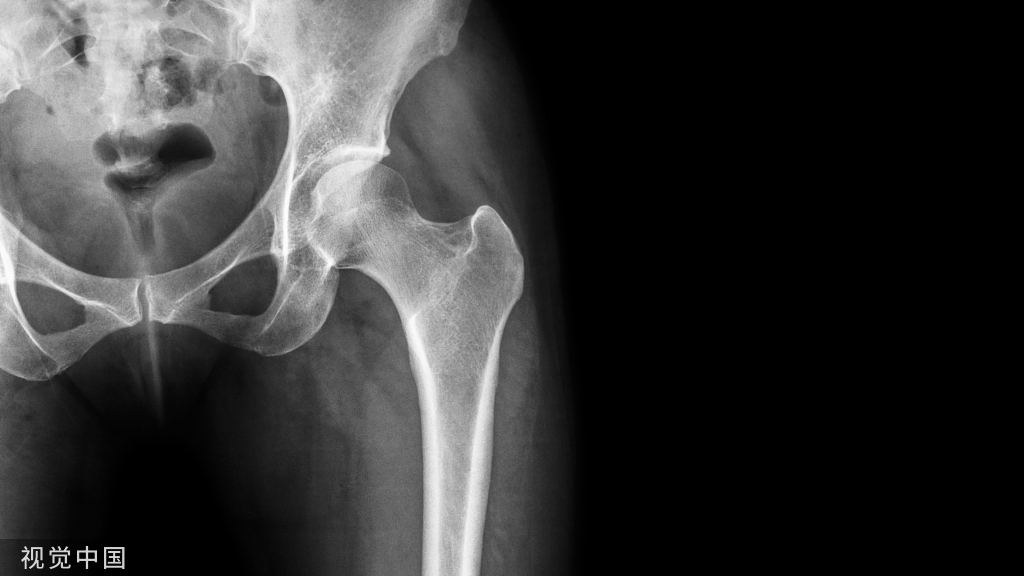

病例特点:女性 32岁,闭合骨折,无合并伤

几个问题1、腓骨固定必须吗?2、腓骨从骨折到骨不连可以避免吗?

3、患者有不适症状吗?

4、同是腓骨骨折,结果大不相同原因?

5、下一步怎么处理腓骨骨折不愈合?